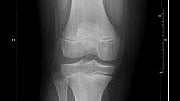

Rheumatoid Arthritis is an inflammatory disease that can cause severe pain and swelling of the joints. But a novel exercise intervention could help improve physical function and quality of life in people struggling with this debilitating condition.

In Australia, rheumatoid arthritis is the second most common form of arthritis, affecting more than 450,000 people. Globally, more than 18 million people live with condition. Women are two-three times more likely to get rheumatoid arthritis than men.